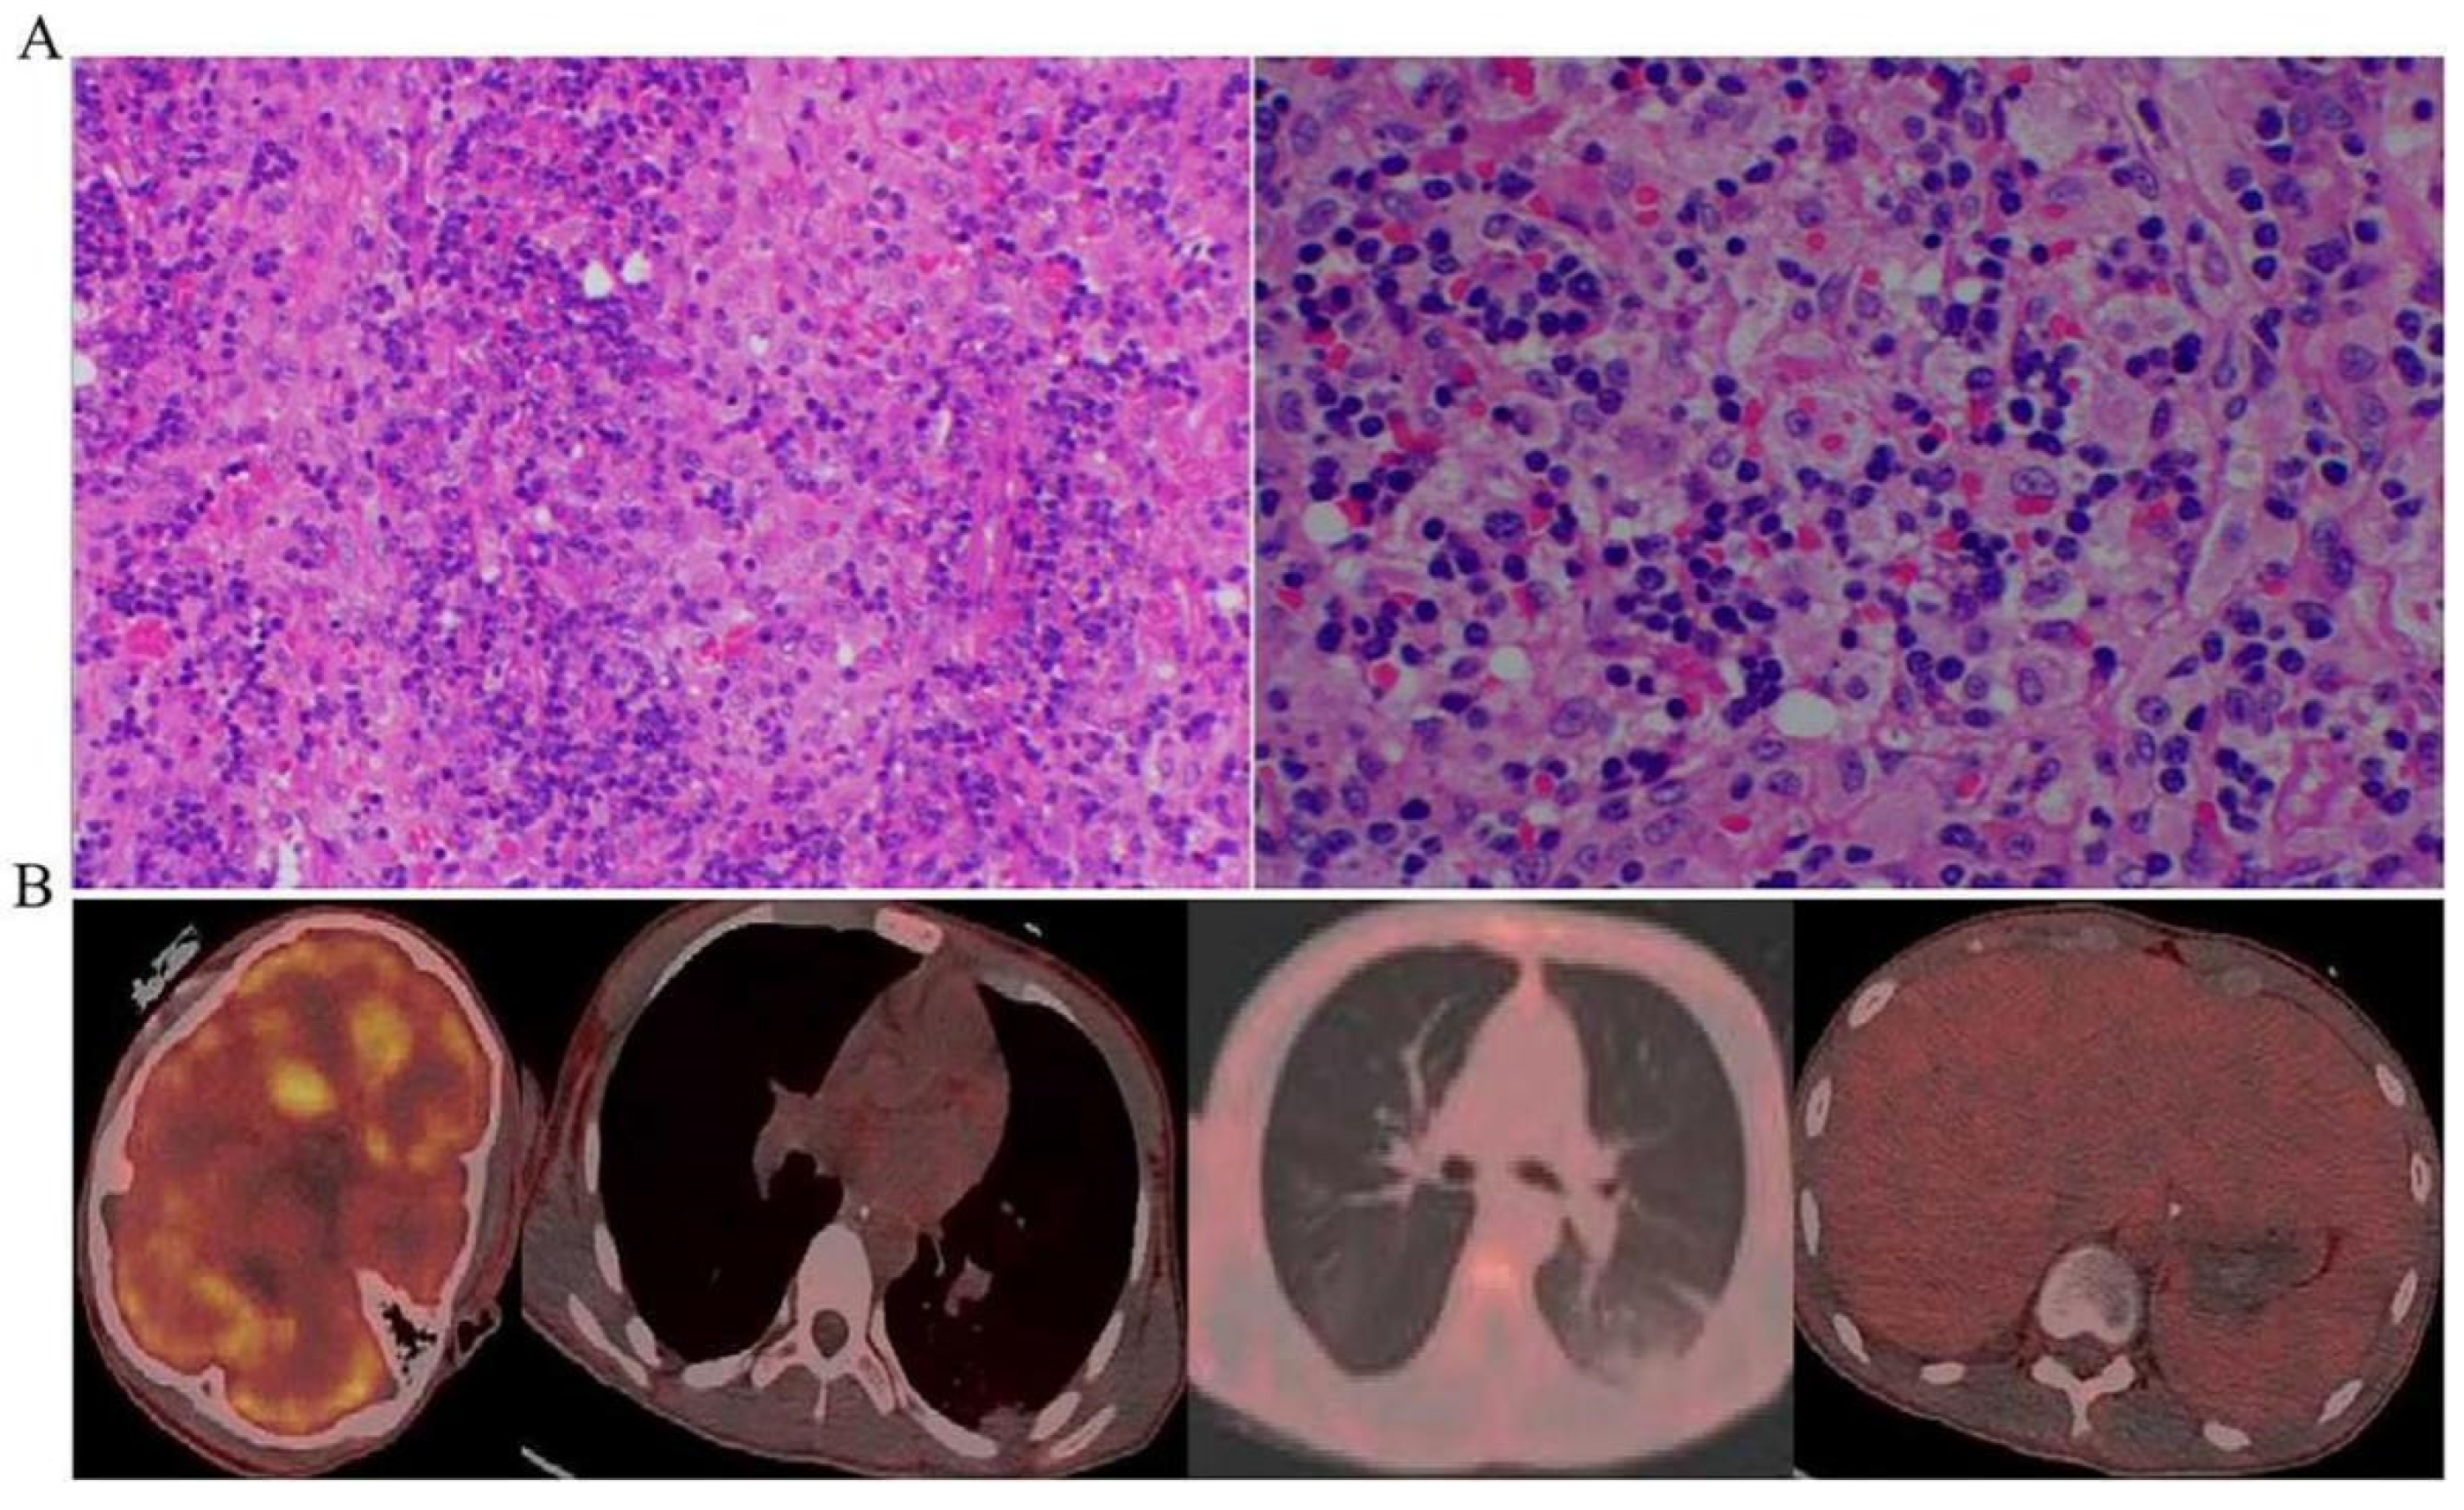

| Hemophagocytosis in bone marrow lymph nodes, spleen, or liver | Yes |